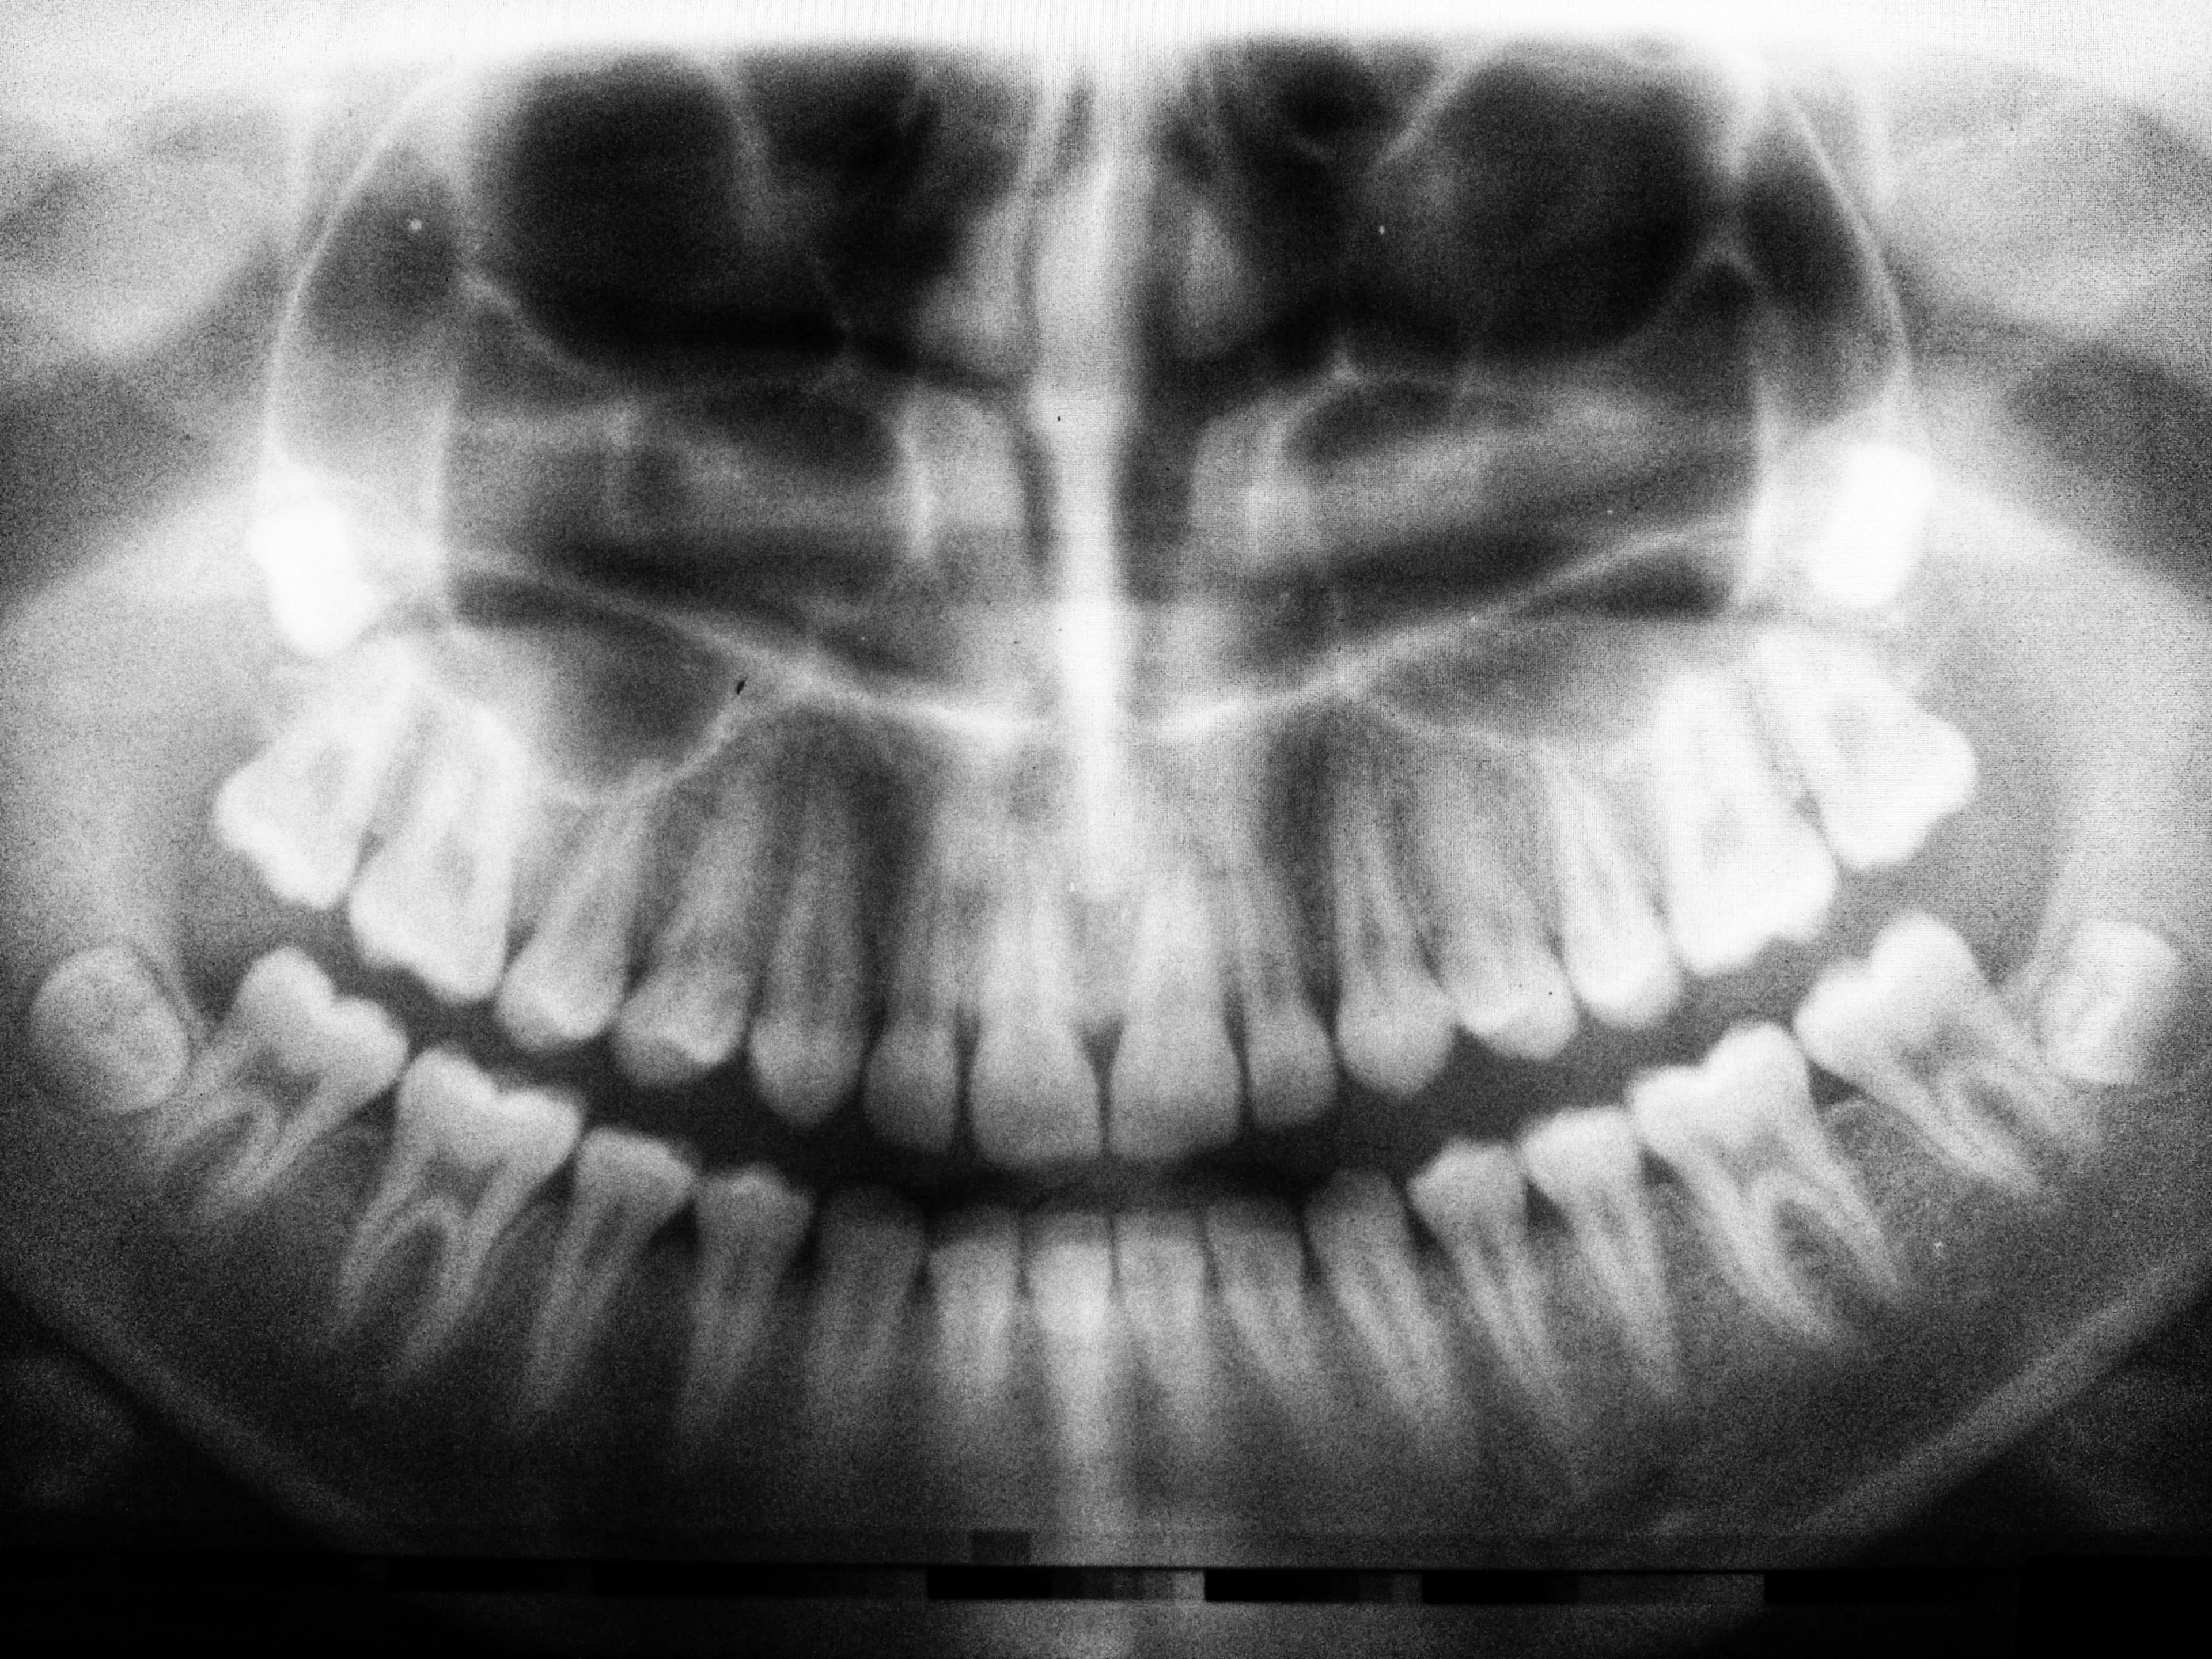

Our clinic offers surgical treatments for maxillofacial trauma, including fractures and injuries to the face and jaw.

There are several possible causes of facial trauma, such as motor vehicle accidents, accidental falls, sports injuries, interpersonal violence, and work-related injuries. Types of facial injuries can range from injuries to the teeth to extremely severe injuries to the skin and bones of the face. In general, facial injuries are classified either as soft tissue injuries (skin and gums), bone injuries (fractures), or injuries in specific regions (such as the orbits, facial nerves, or salivary glands).

By their very nature, facial injuries can cause significant emotional shock and physical trauma to patients. The science and art of managing these injuries require specialized training that includes hands-on experience and an understanding of the long-term impacts of the chosen treatment on the patient's function and appearance. Oral and maxillofacial surgery specialists are well-qualified and possess the necessary expertise to diagnose and treat both minor and major trauma.